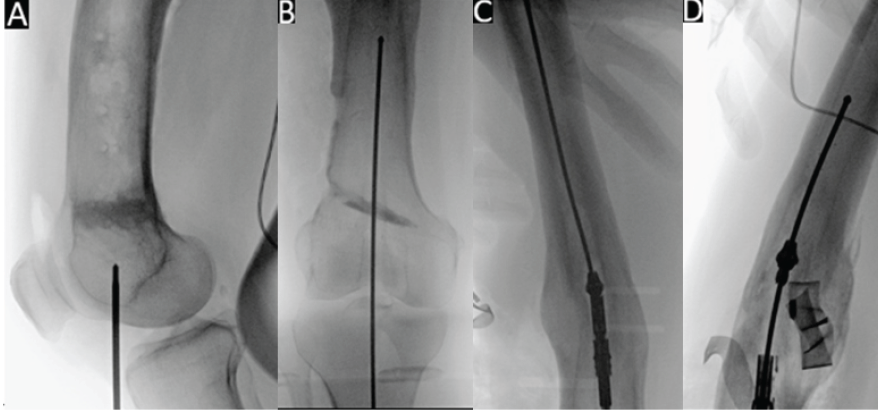

The RIA-2 device was expertly used to obtain intramedullary tissue samples for culture through a retrograde approach due to the residual midshaft deformity and distally located infection. Briefly, a medially parapatellar stab incision was made 4 cm distal to the inferior pole of the patella, and an entry point to the femoral canal was made. Subsequently, an entry guidewire was advanced (Fig. 1a and b), and following measurement of the canal diameter, a 10 mm diameter RIA-2 reamer head was selected. The apparatus was correctly assembled, and the device was inserted into the canal (Fig. 1c). The reamer was advanced slowly, and care was taken to ensure frequent back-and-forth movements to avoid clogging. Fluoroscopy was used to ensure eccentric reaming was avoided. Continuous reaming was carried out, but the surgeon had trouble advancing the RIA, and therefore, reaming was stopped. This is the surgeon’s usual technique to prevent the current complication, which could have been caused by incorrect assembly, clogged flutes, eccentric reaming, and stopping the reamer. A fluoroscopy image was taken, revealing the head had fragmented and dissociated from the rest of the device (Fig. 1d).

Figure 1: Fluoroscopic images of guidewire entry of femoral intramedullary canal (a), followed by advancement of the guidewire (b), then entry of the reamer-irrigator-aspirator (RIA-2) into the canal (c), and dissociation and fragmentation of the RIA-2 head (d).